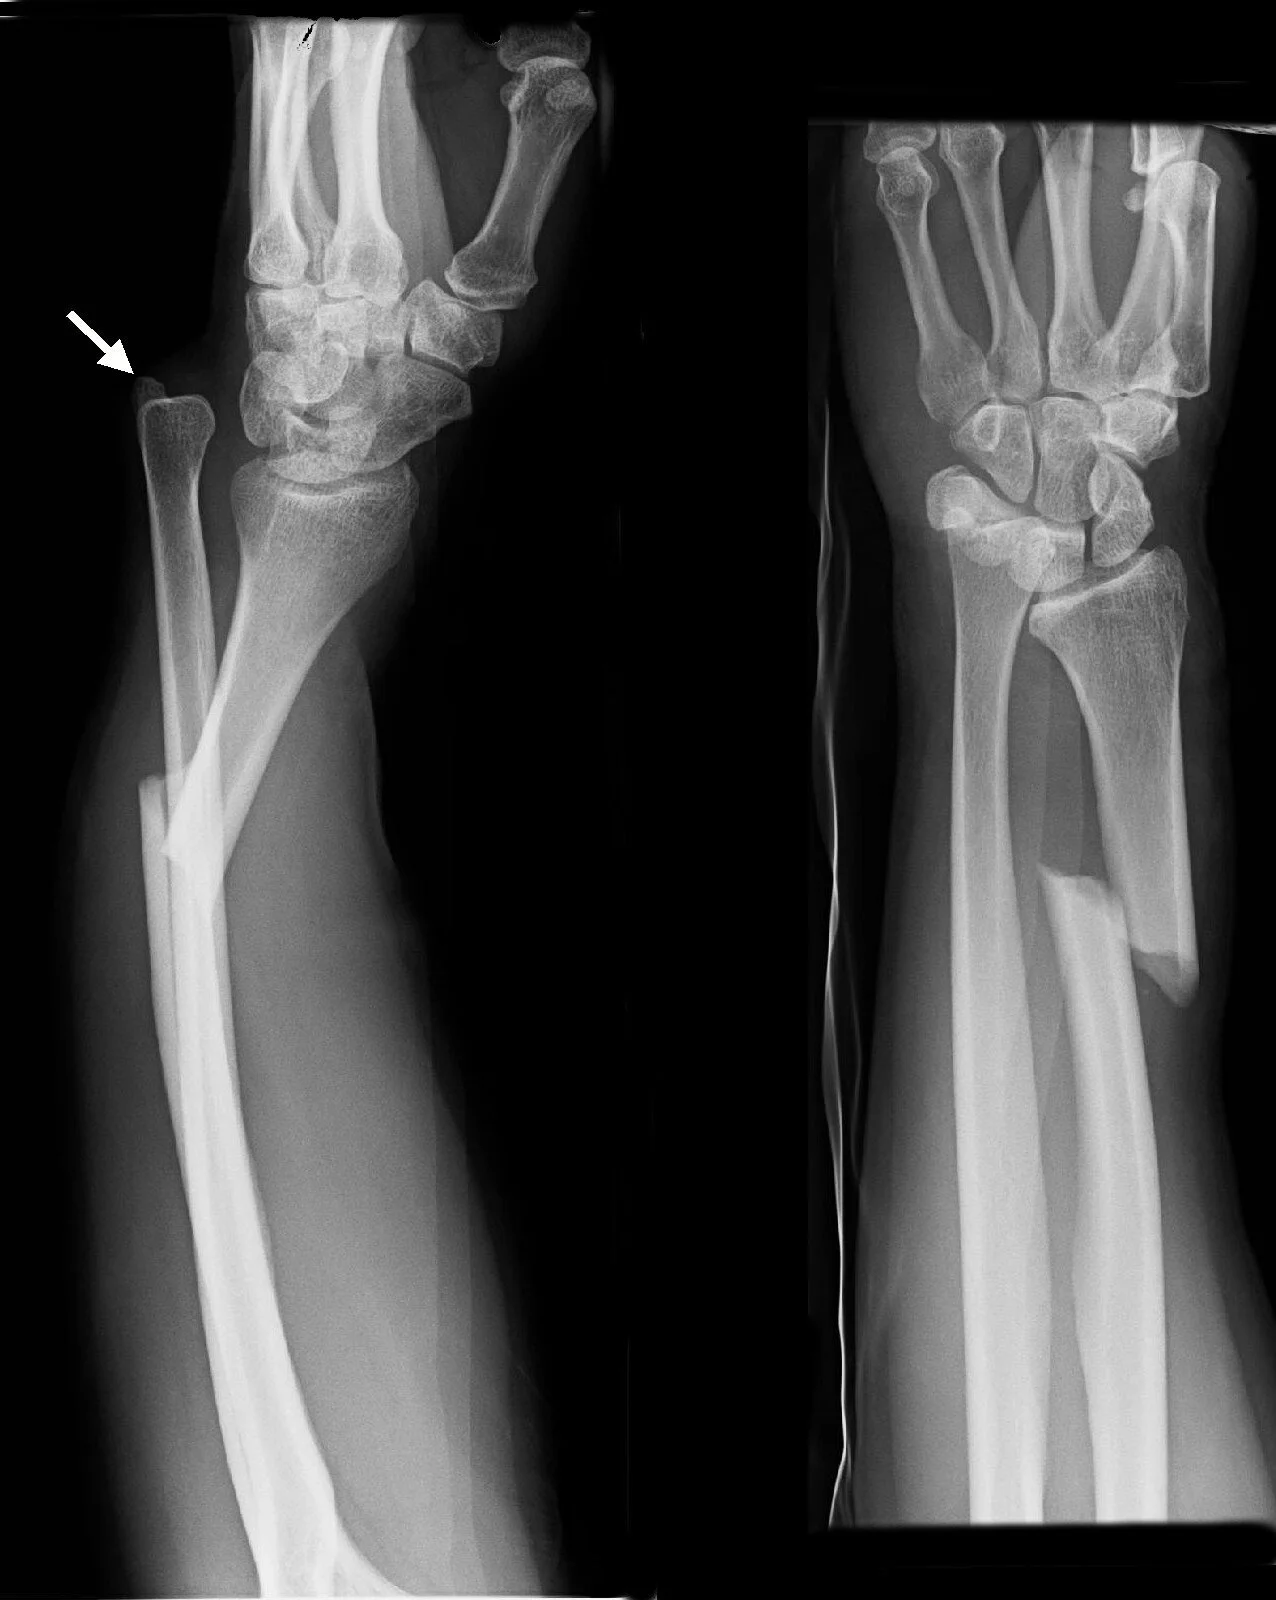

For much of 2012, I was in a campaign called The Devil Made Me Do It. The campaign used a lot of house rules, among them a variant rule for broken bones. In the storyteller's setting, a character who sustained blunt force trauma was at risk of suffering a fracture, and if this injury was healed with ordinary healing magic, then although the visible wound would close, the bone would repair itself in whatever position and shape it was at the time that the spell was cast, generally resulting in a misshapen limb and corresponding penalties. This had no impact on any of the player characters during the campaign, but I do recall that we found one or two NPCs who'd had bones broken, and our party healer had to think a bit outside the box to fix them up on days when he hadn't bothered to memorize Mending, the spell which would repair a bone correctly.

I had mixed feelings about this game mechanic. On the one hand, it was quite clever. Under this rule, an ordinary injury could be used to add a wrinkle to an otherwise easily-resolved situation. Does the cleric heal the NPC badly, or leave them injured until proper healing can be done? Broken bones were never used to advance the story, but they forced the players to think for an extra few seconds during seemingly routine encounters. Players had to juggle their resources a little bit differently. On the other hand, I had some objection to requiring the Mending spell, specifically. In the most popular SRDs, Mending specifically states that it has no effect on creatures, so some people in the group thought it was inappropriate for it to have an effect on broken bones at all. The party's cleric objected to having to memorize an additional spell which, on most days, would prove totally useless... a valid argument, except that it's a zero-level spell available to all major spellcasting classes, and could be cheaply bought in the form of a wand, so it ought to be easy for a party to have it ready once per day. In the end, we all deferred to the storyteller, because it was his game and thus his rules, and the game worked more often than not.